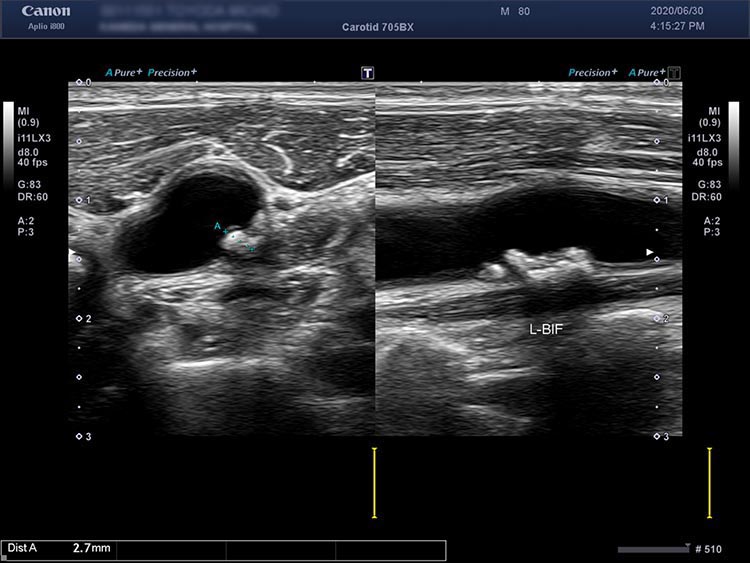

脳梗塞や脳出血の急性期の治療が終わったあと、再発予防のために治療の継続が必要となります。脳血管障害の背景には生活習慣病があることが非常に多く、適切な管理が必要になります。当院では専門医が再発予防のための生活習慣病の管理や専門的な超音波検査を定期的に実施可能です。